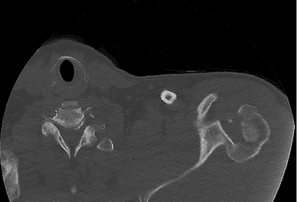

- Imaging:

- X-rays: Standard views to assess the fracture and dislocation.

- CT Scans: For detailed images.

- CT Angiography: Useful for identifying vascular structures in certain fracturepatterns.